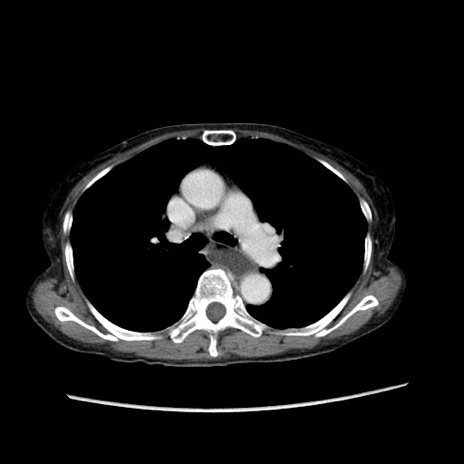

冠状断像

症例25(横断像)

【症例】80歳代女性

【主訴】胸のつかえ感

【現病歴】約9時間前に食後から胸のつかえた感じあり、嘔吐あり、来院。

【既往歴】胃癌(全摘)、胆摘、虫垂炎

【身体所見】心窩部に圧痛あり、反跳痛なし。

【データ】WBC 5700、CRP 0.05